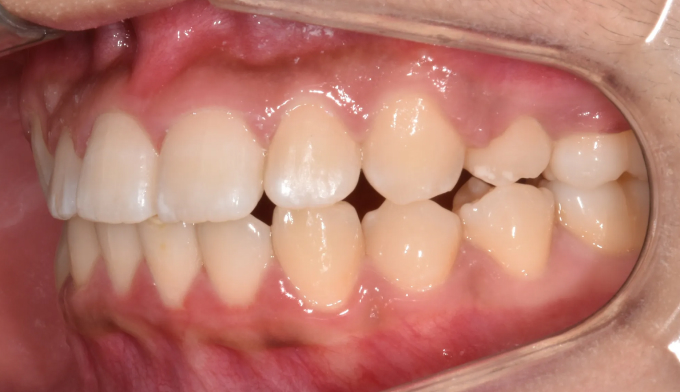

아래 앞니가 선천적으로 하나 없는 경우여서 위아래 가운데선을 맞추지 않고 좌우대칭에 더 신경쓰기로 하였습니다. 위아래 치아 갯수에 차이가 나기 때문에 어쩔 수 없이 어금니 부근의 교합이 완벽하지 못하게 종료될것으로 보였지만 환자 스스로 불편감을 느끼지 못하기 때문에 심미적인면에 더 집중하기로 하고 종료하였습니다.

교합과 심미에 정답은 없습니다.

교합으로인해 불편감을 느끼지 않는다면 환자 스스로의 만족감이 교정치료의 최우선 목표입니다.